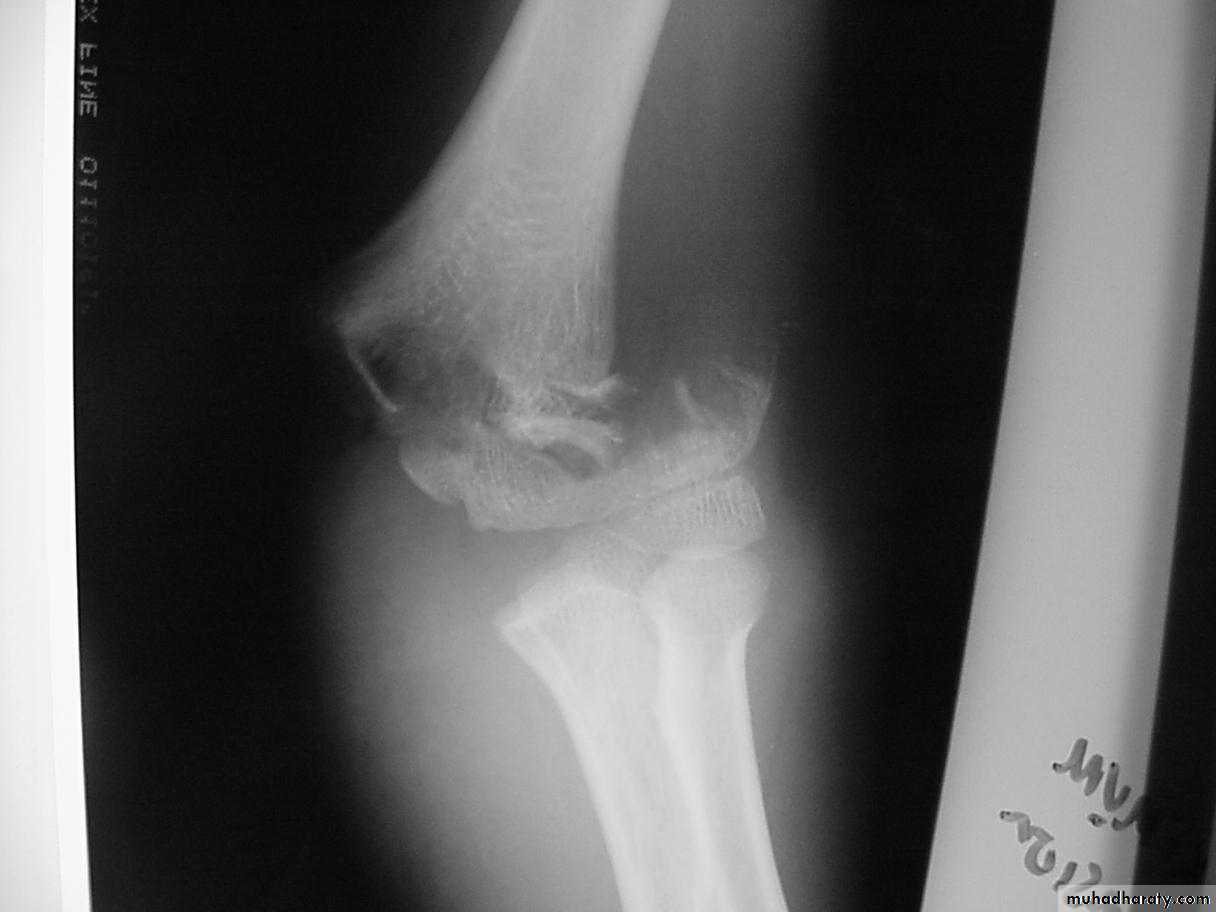

What are the criteria for

fractures?How are Type III extension supracondylar

fractures sub-classified?Yes

Posteromedial vs. Posterolateral

• Nerve, Vessel Injured

• Surgical Approach

• Rate of Complications

In what aspects is there a difference?

What type has a greater

potential for complications?

The rate of complications is greater with the posterolateral fractures.

Posterolateral Pattern

Higher Risk of:1.Vascular injuries

What’s the major concern with the posterolateral pattern ??

What’s the major concern with posterolateral pattern ??

Posterolateral PatternHigher Risk of:

2.Irreducibility

What is the major concern

with the posteromedial fractures ?The radial nerve

is more vulnerable

to injury.